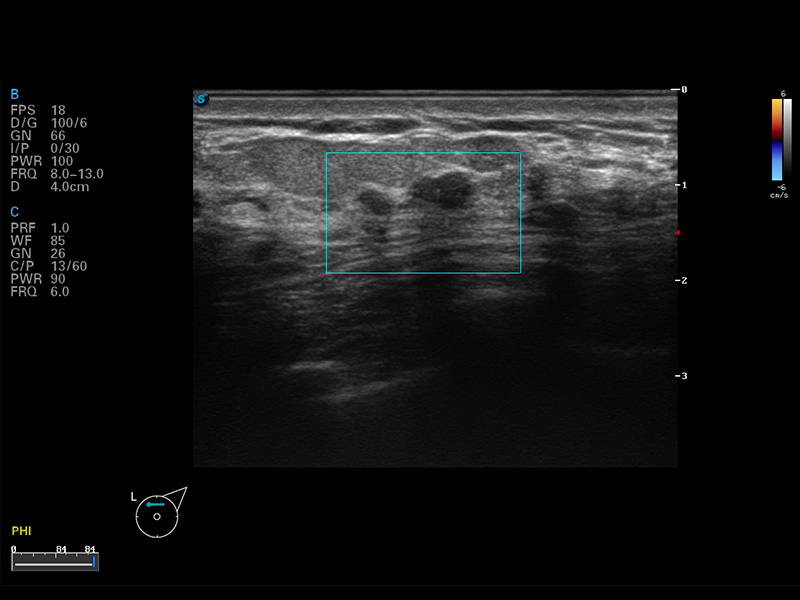

S8 EXP便携式彩色多普勒超声诊断仪是九州酷游研发的高端全身应用型便携彩超。高通道的VIS平台融合可视化(Visual)、智能化(Intelligent)和人性化(Smart)的特点,配以九州酷游自主研发生产的探头大家族,使您能够快速、准确的获得病人信息,提高工作效率的同时减轻疲劳。

μ-Scan微米成像